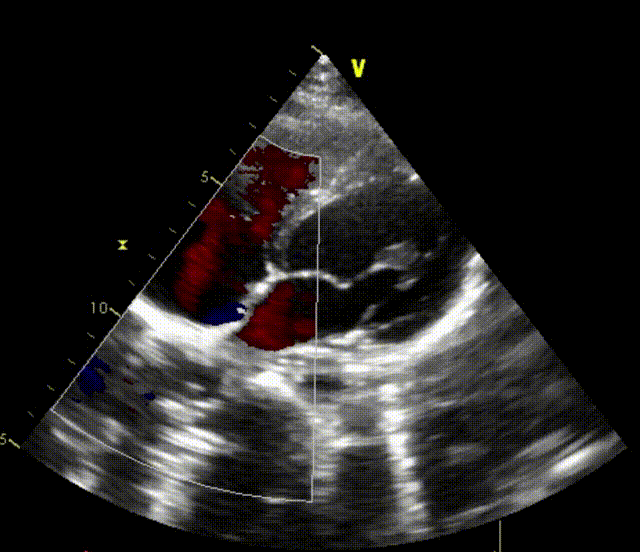

室早RFCA+ASD介入病例(上:术后6个月心超;下:术后12个月心超)

上述良好的短中期随访结果验证了可降解封堵器在儿童ASD介入治疗中的安全性与有效性,期待更长期的随访数据进一步验证远期效果。